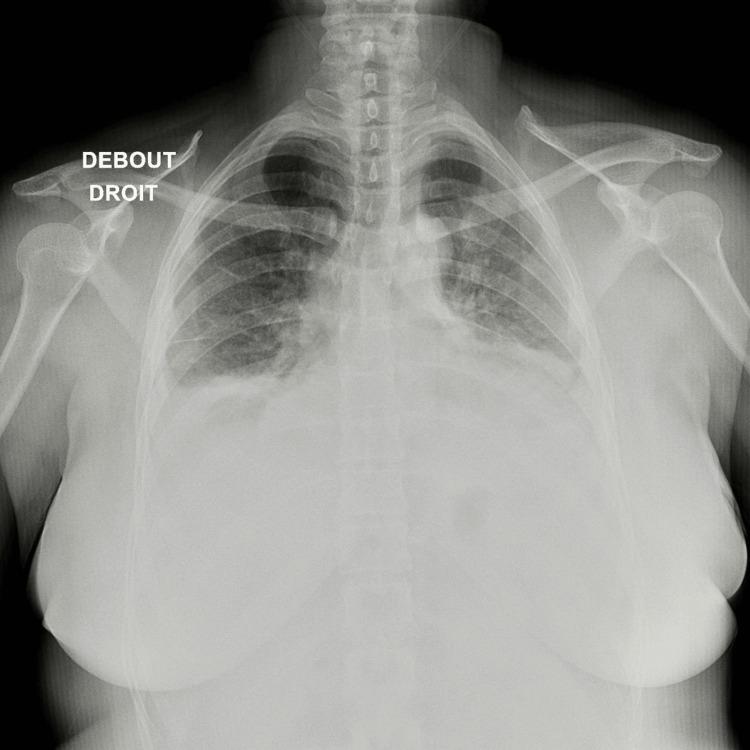

Cryoglobulinemic vasculitis is a rare small-vessel vasculitis leading to multi-organ dysfunction, often associated with chronic infections like hepatitis C virus (HCV), and autoimmune disorders. Most cases involve mixed monoclonal or polyclonal immunoglobulins, presenting symptoms such as purpura, arthralgias, and weakness. Severe organ involvement, particularly cardiac, is rare but potentially life-threatening. We report the case of a 48-year-old woman without prior medical history who presented with acute dyspnea, generalized petechial purpura, and signs of global heart failure. Imaging and laboratory findings indicated cardiomegaly, pericardial effusion, and significant nephrotic syndrome with renal failure. The diagnosis of cryoglobulinaemia was confirmed through histology and serology, showing monoclonal IgM with kappa hypergammaglobulinaemia and complement consumption. Treatment included various immunosuppressants, corticosteroids, and rituximab combined with renal replacement therapy. Following the initiation of treatment and proper management of heart failure, the patient's condition significantly improved. Cardiac involvement in cryoglobulinemic vasculitis, though rare, can lead to severe heart failure. This often involves necrotizing vasculitis of the coronary arteries or systemic inflammation damaging the cardiac muscle, as observed here. Cardiac manifestations with immunosuppressive therapy are reversible despite a poor long-term prognosis for patients with cardiac lesions. In conclusion, cryoglobulinemic vasculitis has a grim prognosis due to its multi-organ impact and the severity of the lesions. Early and aggressive treatment is essential to manage life-threatening acute presentations, even before confirming the diagnosis biologically or histologically.

冷球蛋白血症性血管炎是一种罕见的小血管血管炎,可导致多器官功能障碍,常与丙型肝炎病毒(HCV)等慢性感染以及自身免疫性疾病相关。大多数病例涉及混合性单克隆或多克隆免疫球蛋白,表现为紫癜、关节痛和乏力等症状。严重的器官受累,尤其是心脏受累,虽罕见但可能危及生命。我们报告一例48岁无既往病史的女性,她出现急性呼吸困难、全身性瘀点性紫癜及全心衰体征。影像学和实验室检查结果显示心脏扩大、心包积液以及伴有肾衰竭的显著肾病综合征。通过组织学和血清学检查确诊为冷球蛋白血症,显示单克隆IgM伴κ轻链高球蛋白血症及补体消耗。治疗包括多种免疫抑制剂、糖皮质激素以及利妥昔单抗联合肾脏替代治疗。在开始治疗并对心力衰竭进行恰当管理后,患者病情显著改善。冷球蛋白血症性血管炎中的心脏受累虽罕见,但可导致严重心力衰竭。如此处所见,这通常涉及冠状动脉坏死性血管炎或系统性炎症对心肌的损害。尽管心脏病变患者的长期预后不佳,但免疫抑制治疗后的心脏表现是可逆的。总之,冷球蛋白血症性血管炎因其对多器官的影响及病变的严重性,预后严峻。即使在生物学或组织学确诊之前,早期积极治疗对于处理危及生命的急性表现至关重要。